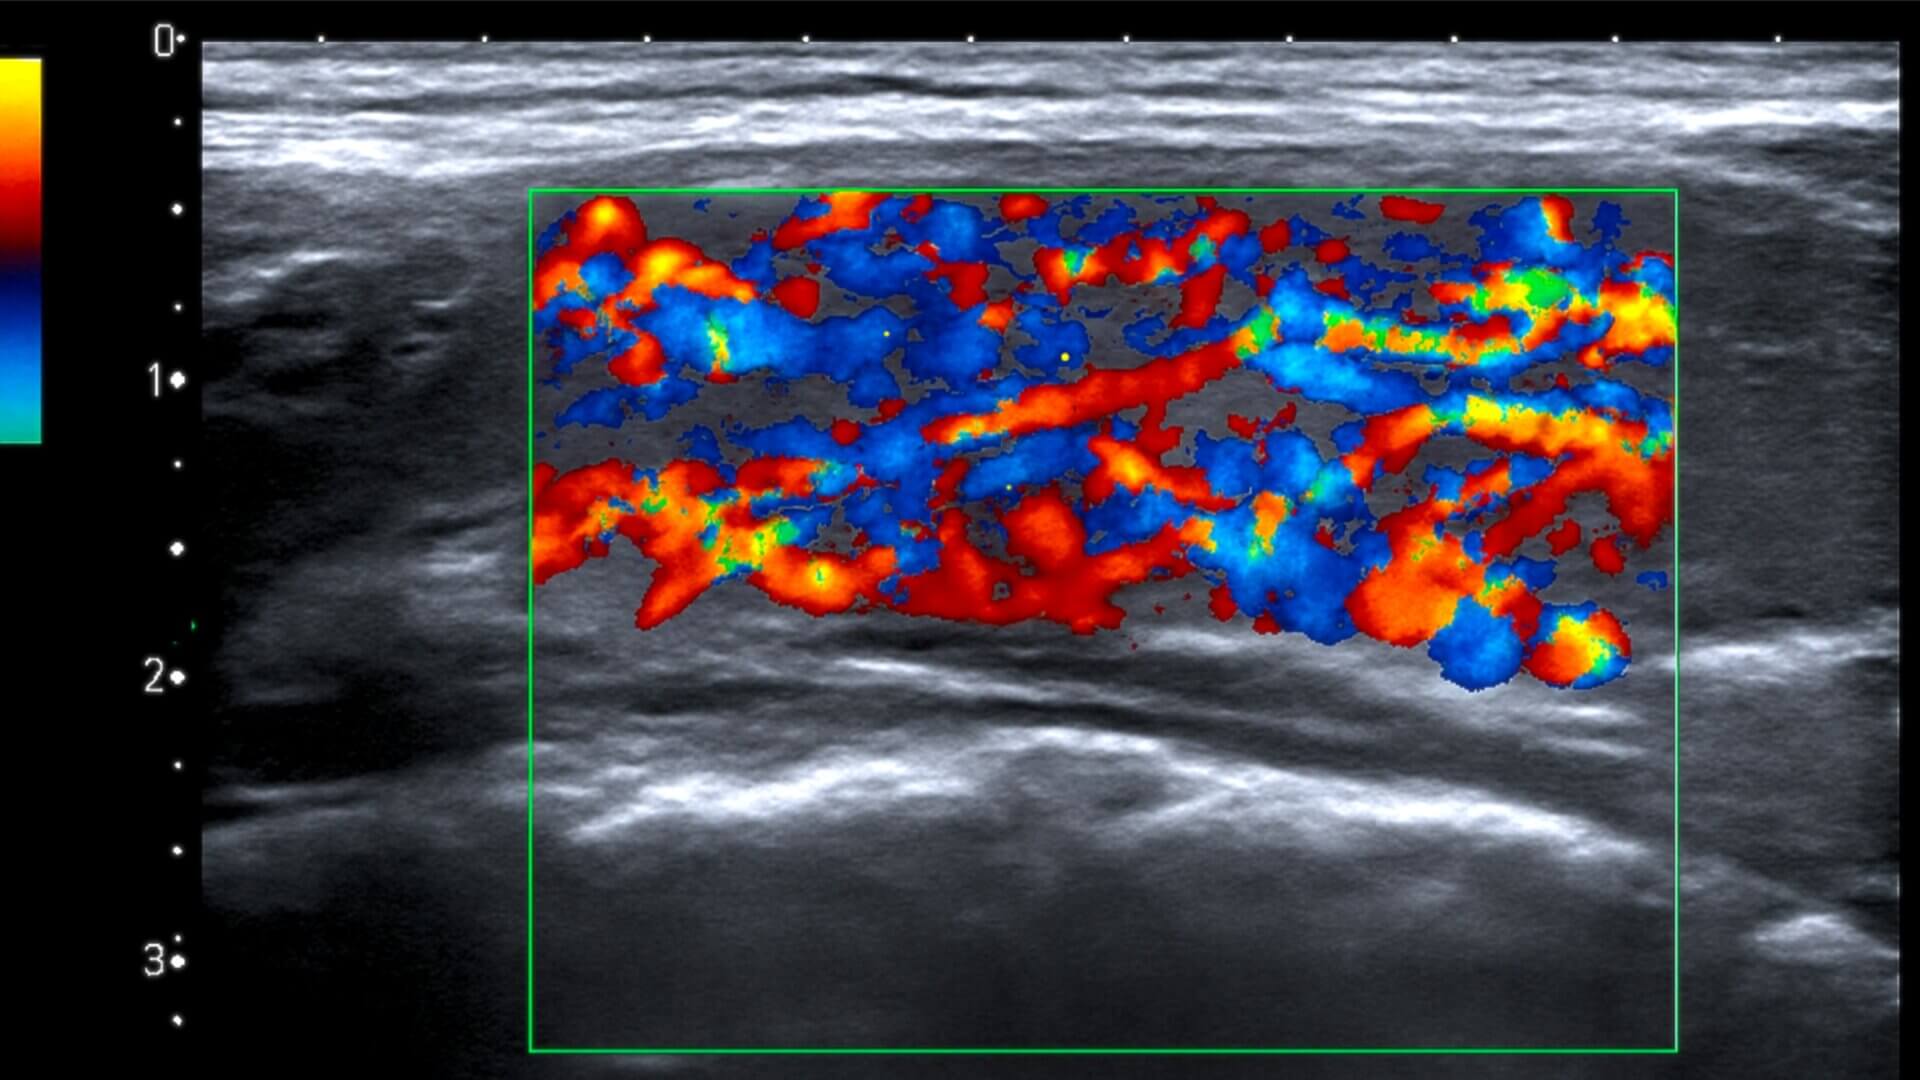

Das vaskuläre Inferno bezeichnet ein sonographisches Zeichen in der Sonographie der Schilddrüse, bei dem es durch eine stark erhöhte Durchblutung des Schilddrüsenparenchyms im Rahmen eines Morbus Basedow zu einem unübersichtlichen Gesamtbild mit dynamischen Strömungsmustern kommt.

KI-generiert, lizenziert unter CC BY-NC-SA 4.0